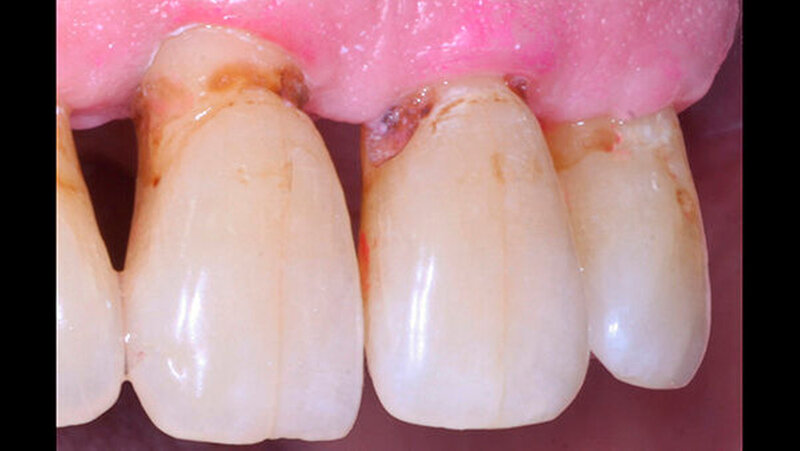

Durch Fortschritte in der zahnärztlichen Prävention und Therapie können Senioren heute ihre eigenen Zähne bis in ein hohes Alter behalten. Aufgrund altersbedingter Veränderungen, wie zum Beispiel der Rückbildung des Zahnhalteapparates, besteht für die erhaltenen Zähne jedoch ein hohes Risiko für die Entwicklung von Wurzelkaries (Abbildung 1).

In der aktuellen Deutschen Mundgesundheitsstudie (DMS V) konnte gezeigt werden, dass insbesondere Zähne von pflegebedürftigen Senioren häufig Wurzelkaries aufweisen. Da Wurzelkariesläsionen in unzugänglichen Bereichen wie Approximalräumen schwer zu therapieren sind (Abbildung 2) und die Therapieoptionen bei pflegebedürftigen Patienten meist eingeschränkt sind, ist es von großer Bedeutung, der Entstehung von Wurzelkaries bei Senioren vorzubeugen. Daher war es das Ziel unserer Untersuchung, den Effekt von unterschiedlichen kariesprophylaktischen Substanzen in verschiedenen Darreichungsformen (als Lack oder Spülung) auf die Entstehung von Wurzelkaries in einem kariogenen Biofilmmodell zu untersuchen.